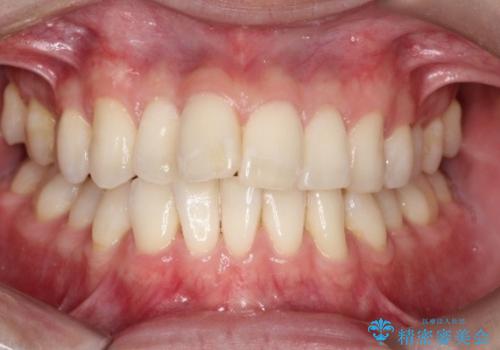

前歯の重なりとガタガタをマウスピースで改善した症例

初診時の歯並びの状態としては、上下ともに前歯部の中等度のがたつきがあり、上の前歯が重なっている状態でした。

また元々下の前歯は1本少なく、歯の本数が少ないことを前提とした矯正治療を行いました。

抜歯は必要なく、マウスピース矯正にて治療を行っています。

見た目、嚙み合わせ及び、治療期間や施術内容に大変ご満足いただきました。